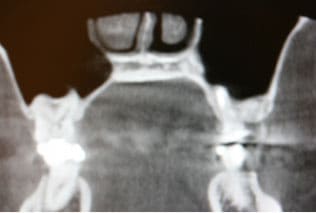

CASE04 歯が原因で起きる副鼻腔炎(歯性上顎洞炎)

鼻の両サイドにある上顎洞という副鼻腔の粘膜が、上顎臼歯部の不適切な根管治療や歯周病などにより炎症を起こし、鼻閉感や頬部痛などを引き起こします。慢性的な炎症ですと、さほど痛みも無く発見が遅れる場合が多く、主に片側で起こります(鼻が原因の副鼻腔炎は両側で発症)。急性症状になると鼻から膿が出たり、激しい痛みを伴いよく耳にする蓄膿症という病気になります。

左側のCTの写真は、不適切な根管治療により(根管に詰める材料が副鼻腔に突き抜けている状態)慢性副鼻腔炎を起こし、片側の強い鼻閉感と左上の第一大臼歯の痛みを主訴にいらした患者様です。根管充填材料の突き抜けている状態と、副鼻空の粘膜の肥厚がCTより確認できました。

慎重に根管の詰め物を撤去し、管から膿抜きをして殺菌消毒をした結果、副鼻腔の粘膜の腫れが消失してきているのが分かります。